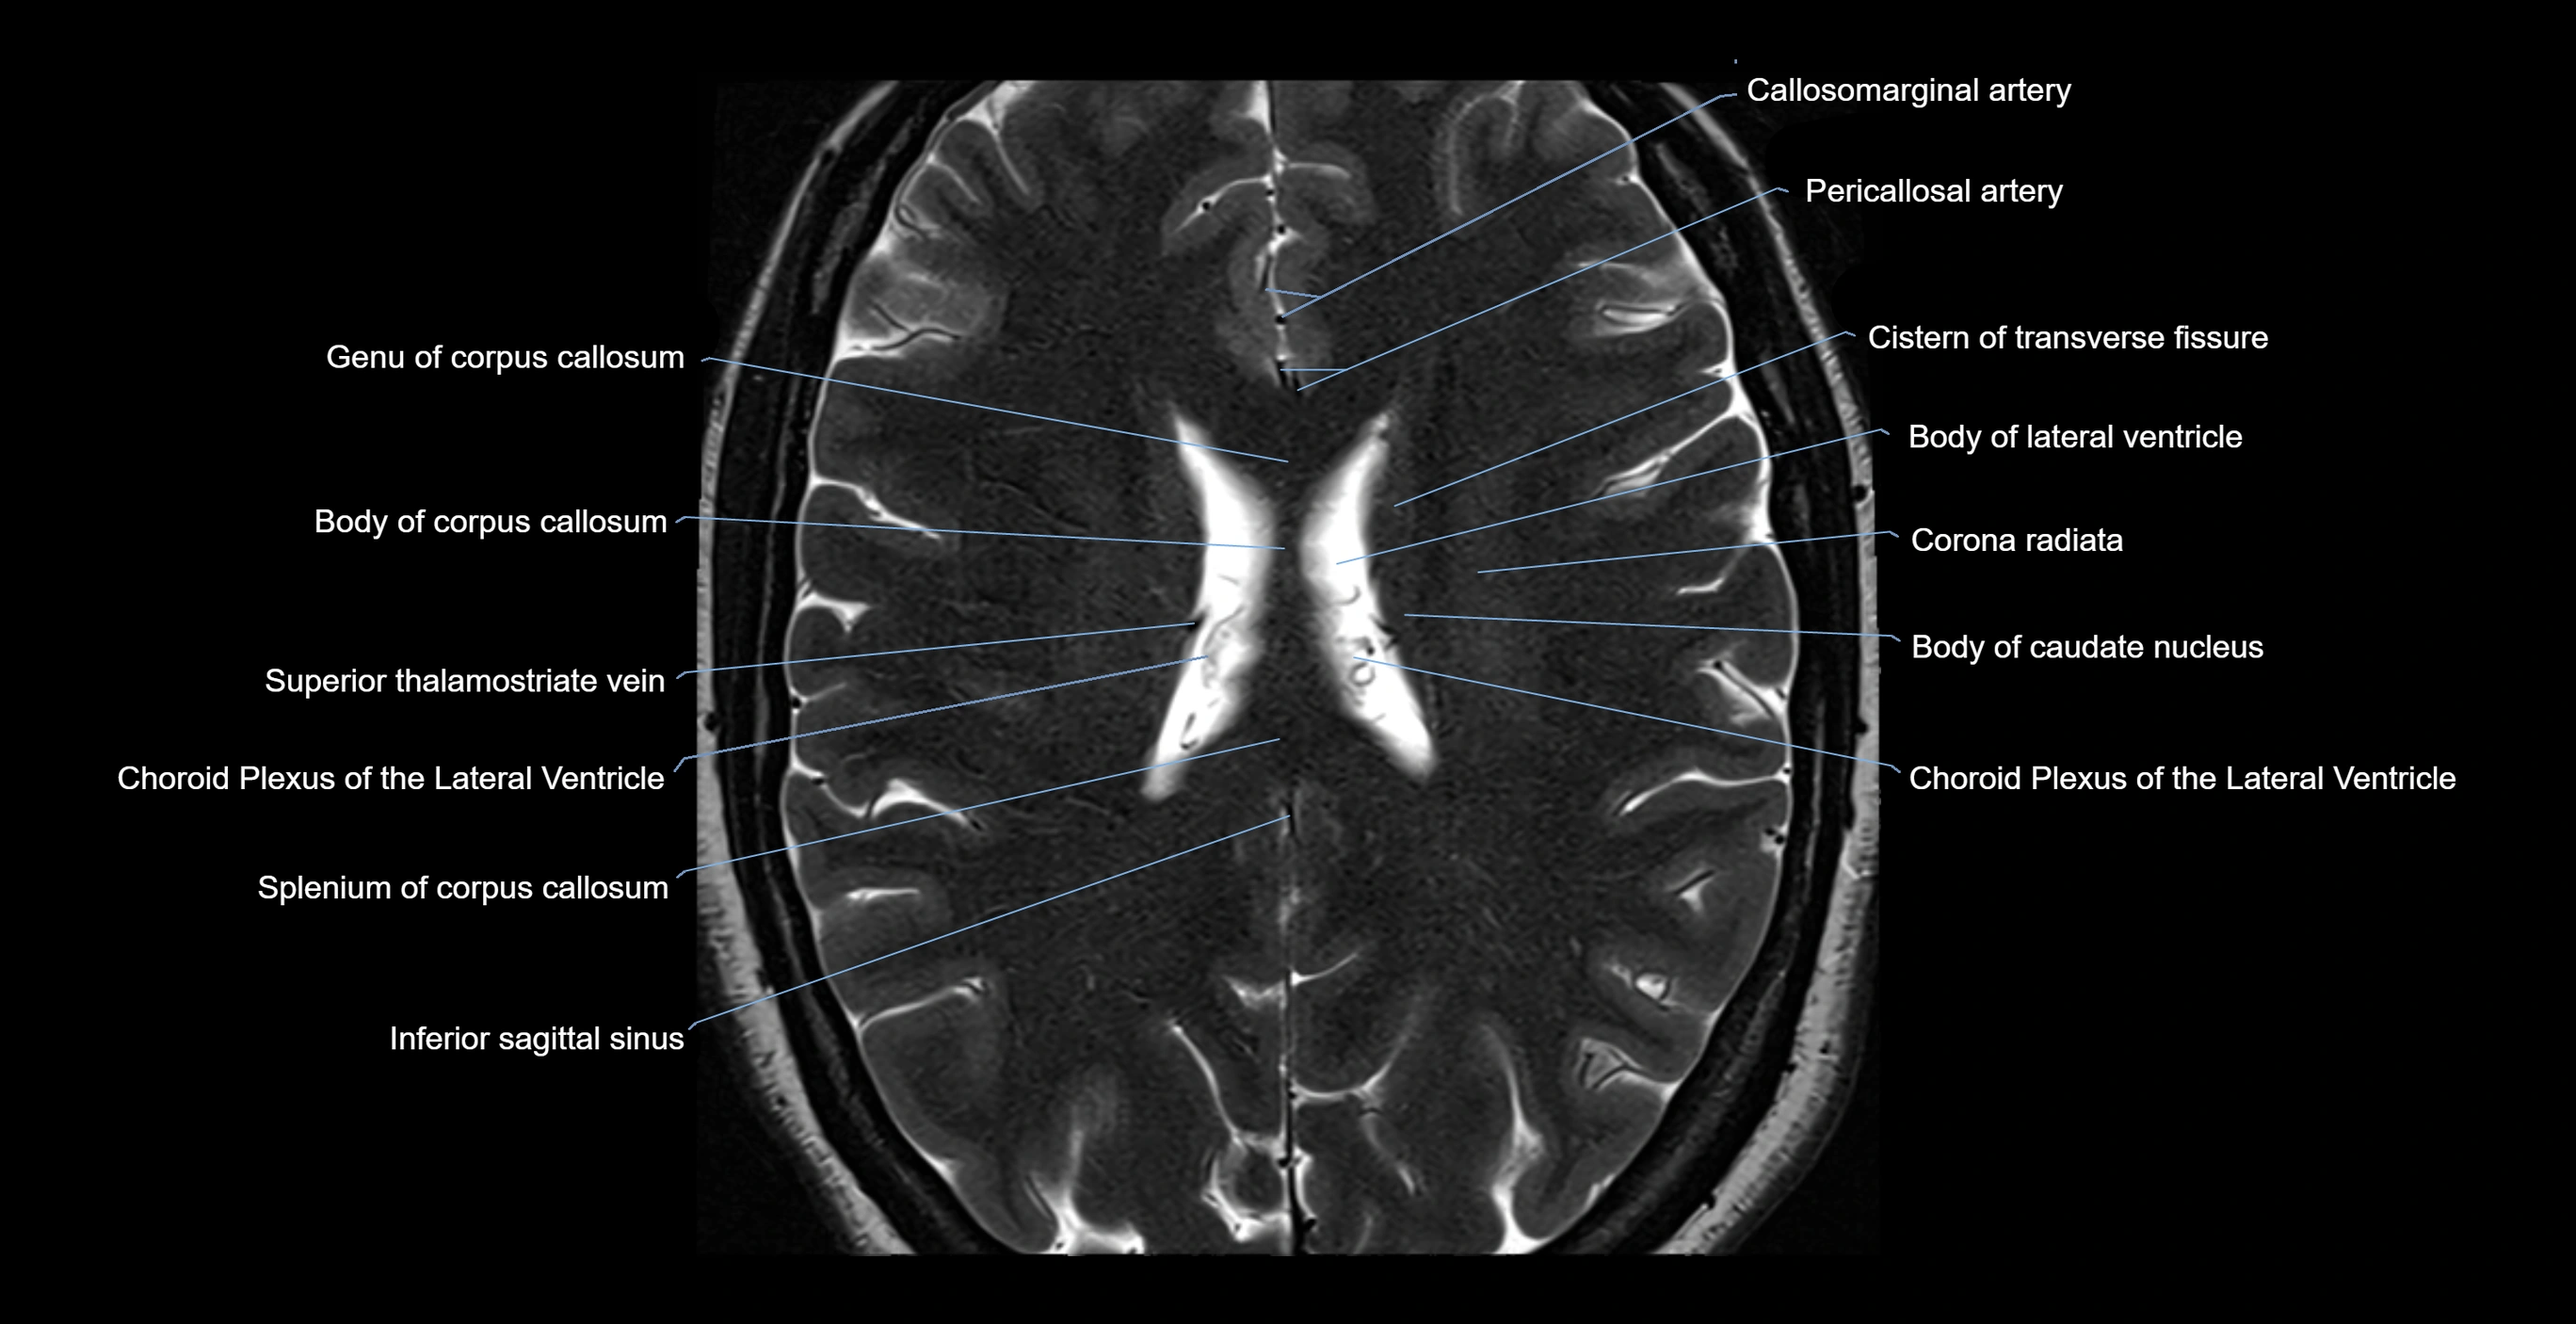

MRI images